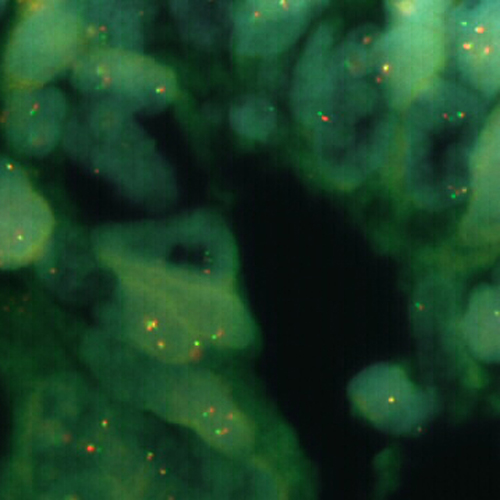

Human prostate: immunohistochemical staining for p63. p63: clone 7JUL

p63 is a nuclear transcription factor, reported to be expressed in a number of normal tissues including proliferating cells of the epithelium, cervix, urothelium and prostate. p63 is also reported to be expressed in most poorly differentiated squamous cell carcinomas.